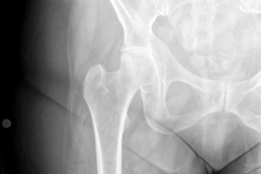

This 79-year-old woman fell in the street after getting off the bus, sustaining the above injury. Can you des…

Can you describe the radiographs and tell me what your immediate concerns would be? These are AP and lateral …